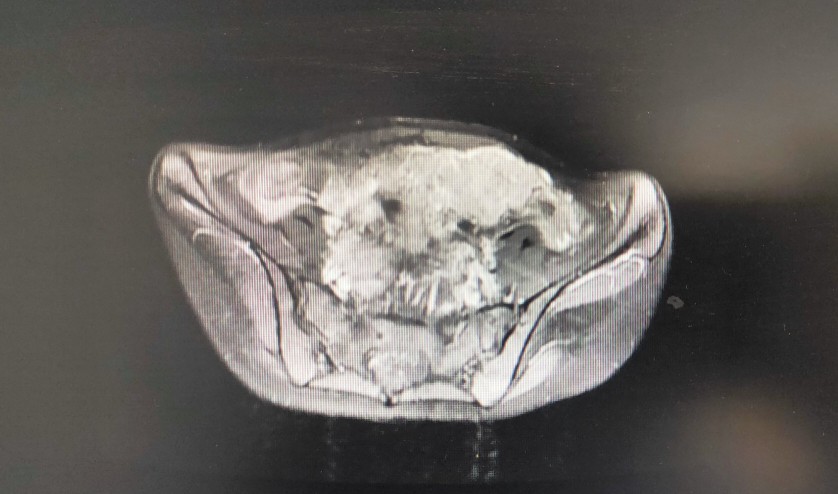

一位22岁的年轻女性,于2020年2月初诉下腹部隐痛,伴腹胀,乏力,就诊门诊妇科,查体发现左下腹一质硬包块,行盆腔核磁共振示:盆腔及子宫腔内多发占位。便收入院治疗,入院做上腹部CT示:肝脏多发低密度占位,考虑转移性病变。

入院后行手术治疗,术后病理:子宫内膜样癌,FⅠGOII级,侵及子宫壁全层,脉管内癌栓,双侧卵巢,左右宫旁,大网膜见癌累及。目前分期晚,预后差,需行术后辅助治疗。